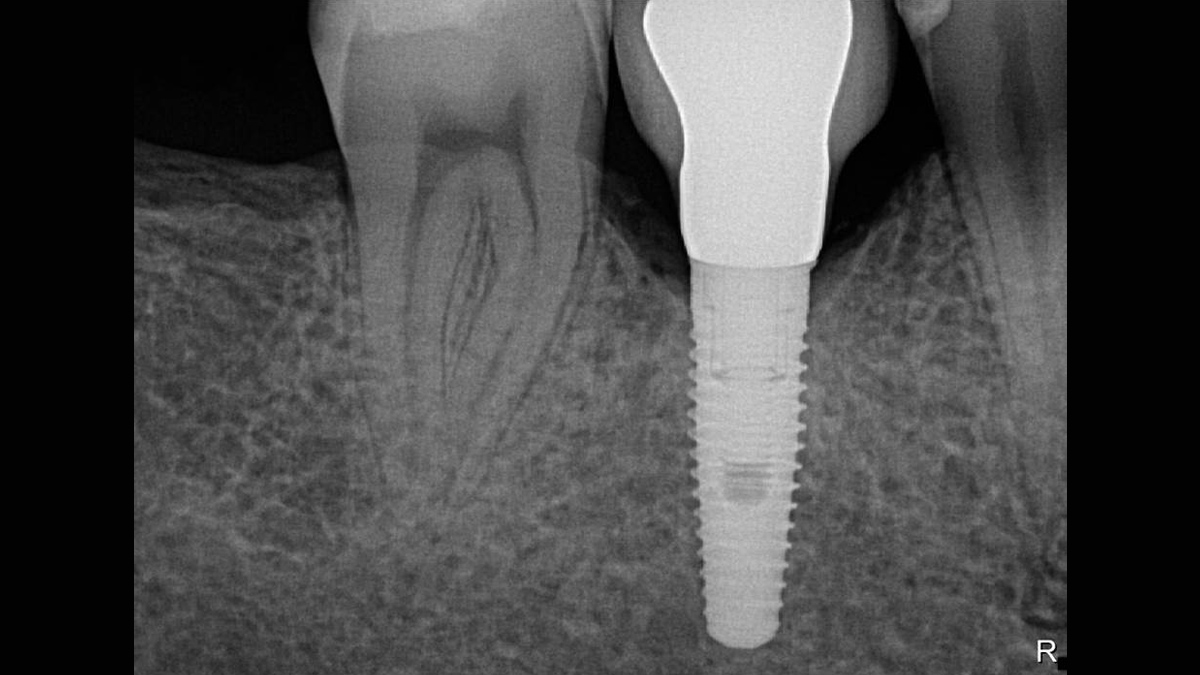

Working with Schick 33: Filtering enhancements

With Schick 33 sensors you have the option of five different filtering options: General Dentistry, Endodontics, Periodontics, Restorative and Hygiene. These clinically specific views are designed to optimize your diagnosis, enhancing the image to suit your needs.

Schick 33 - Gallery of Sample Images